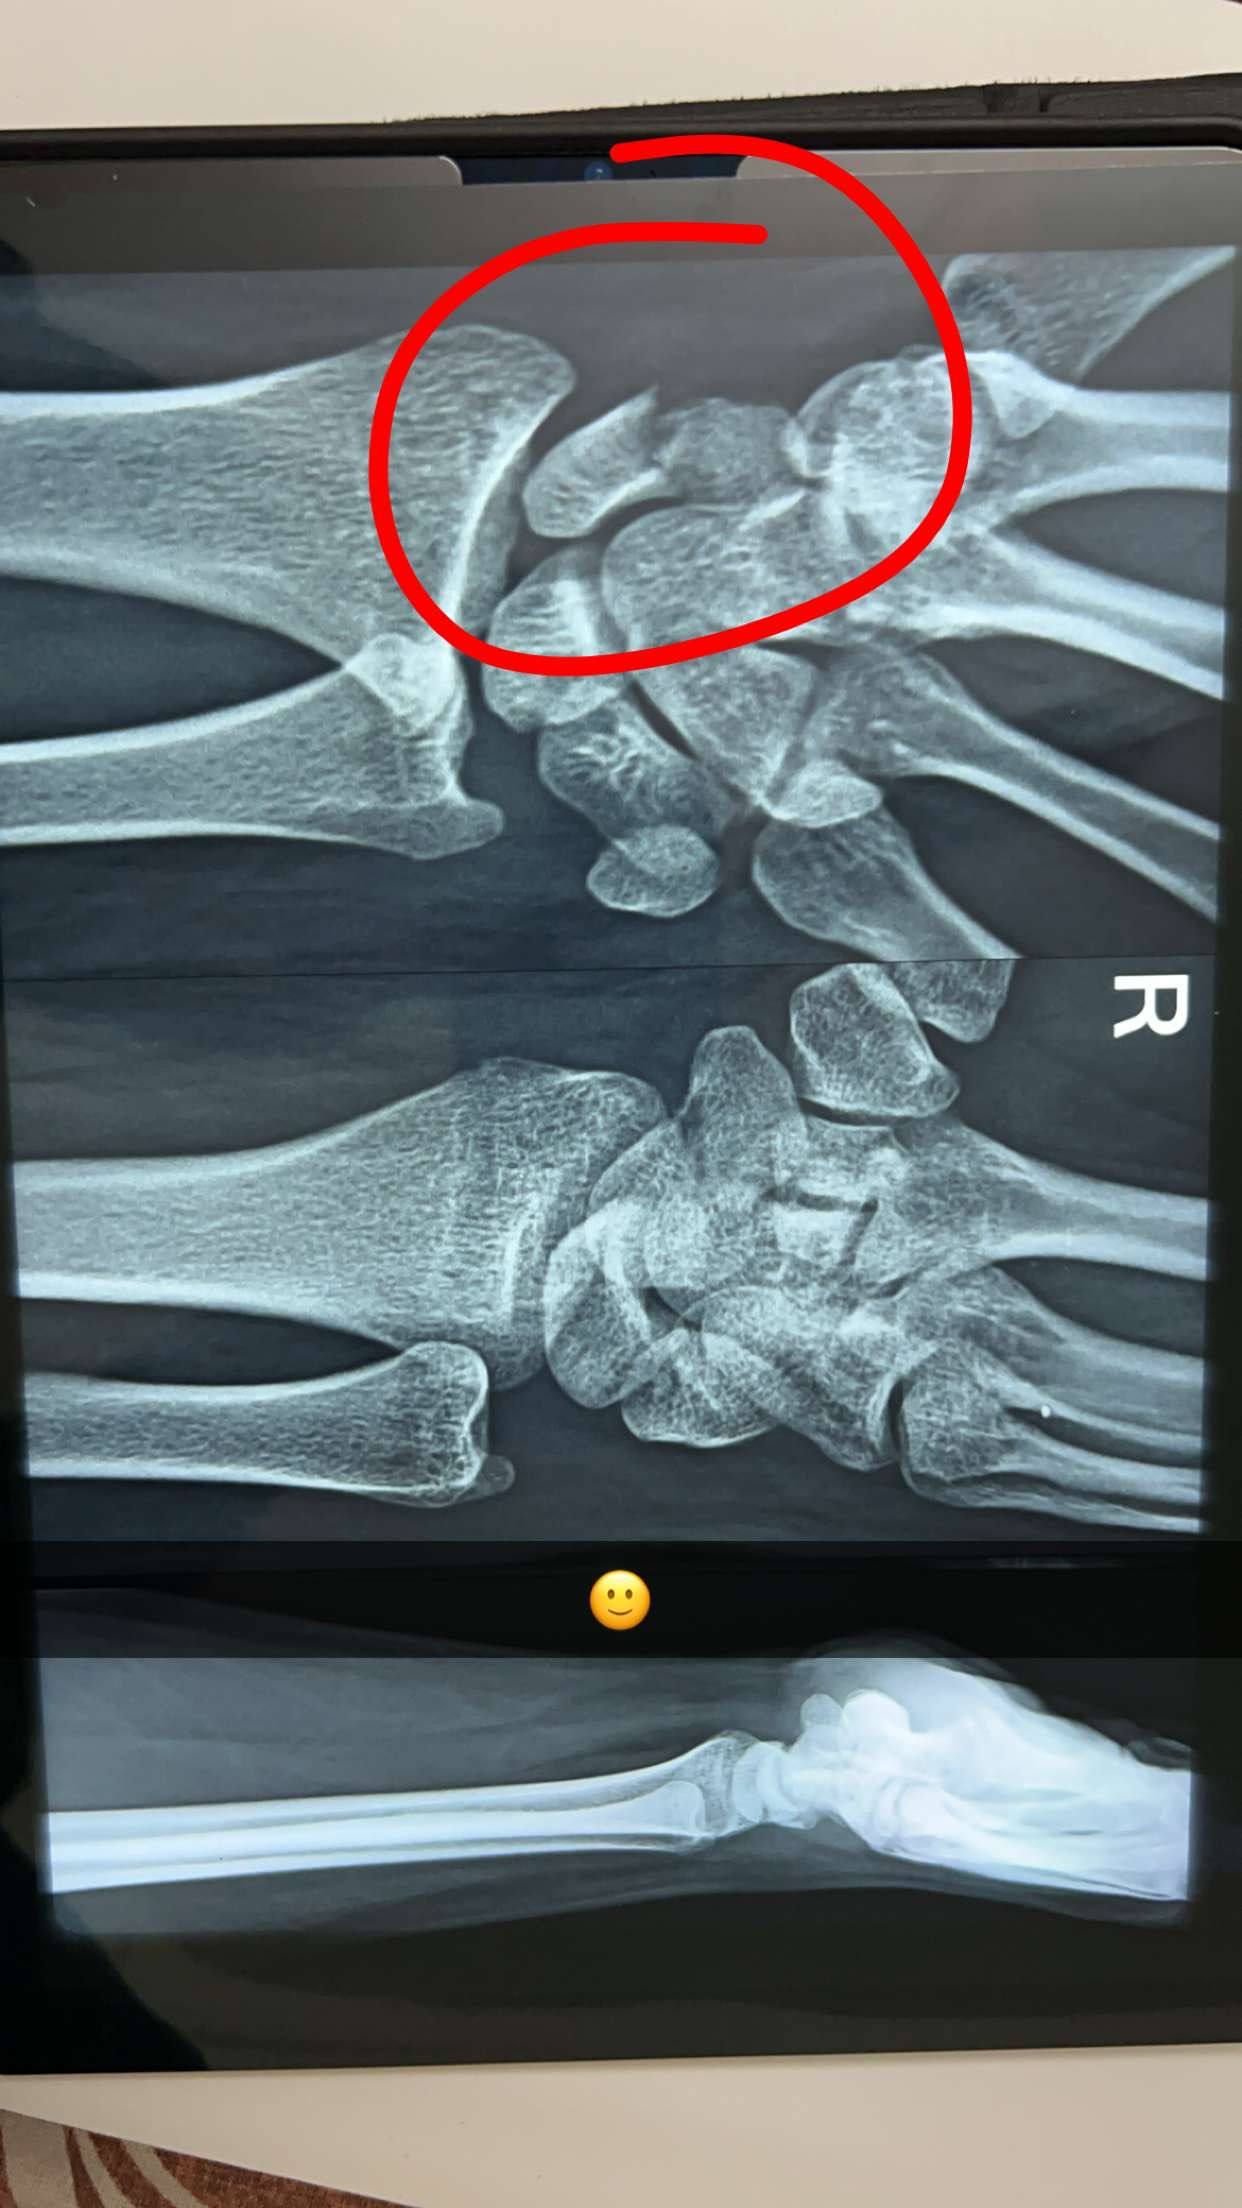

sir aaj se 6 months pehle mera accident hoogya tha jiski wajeh se i had a scaphoid fracture in my right hand

till today i haven’t done any plaster or any treatment nor do i suffer from pain but drs ne bola hai ki operation krwana padega….but my hand works exactly the same without any pain and movement loss cann you please tell me what to do